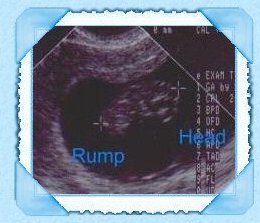

Our first ultrasound of our baby.

There is a BABY in there giggle!

PrettyMoon 3 months pregnant.

As you can tell I marked the ultrasounds so you can tell :)